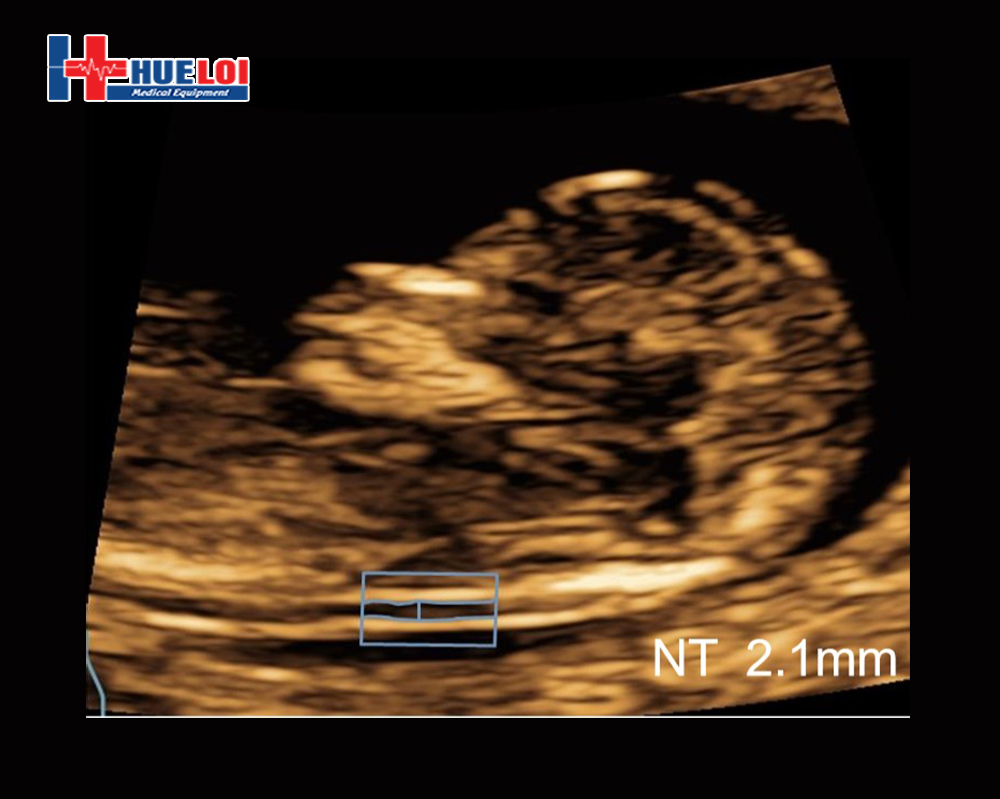

Tự động dò tìm bờ khoang ống độ mờ da gáy NT và hiển thị kết quả NT theo phương pháp chuẩn "In to In"